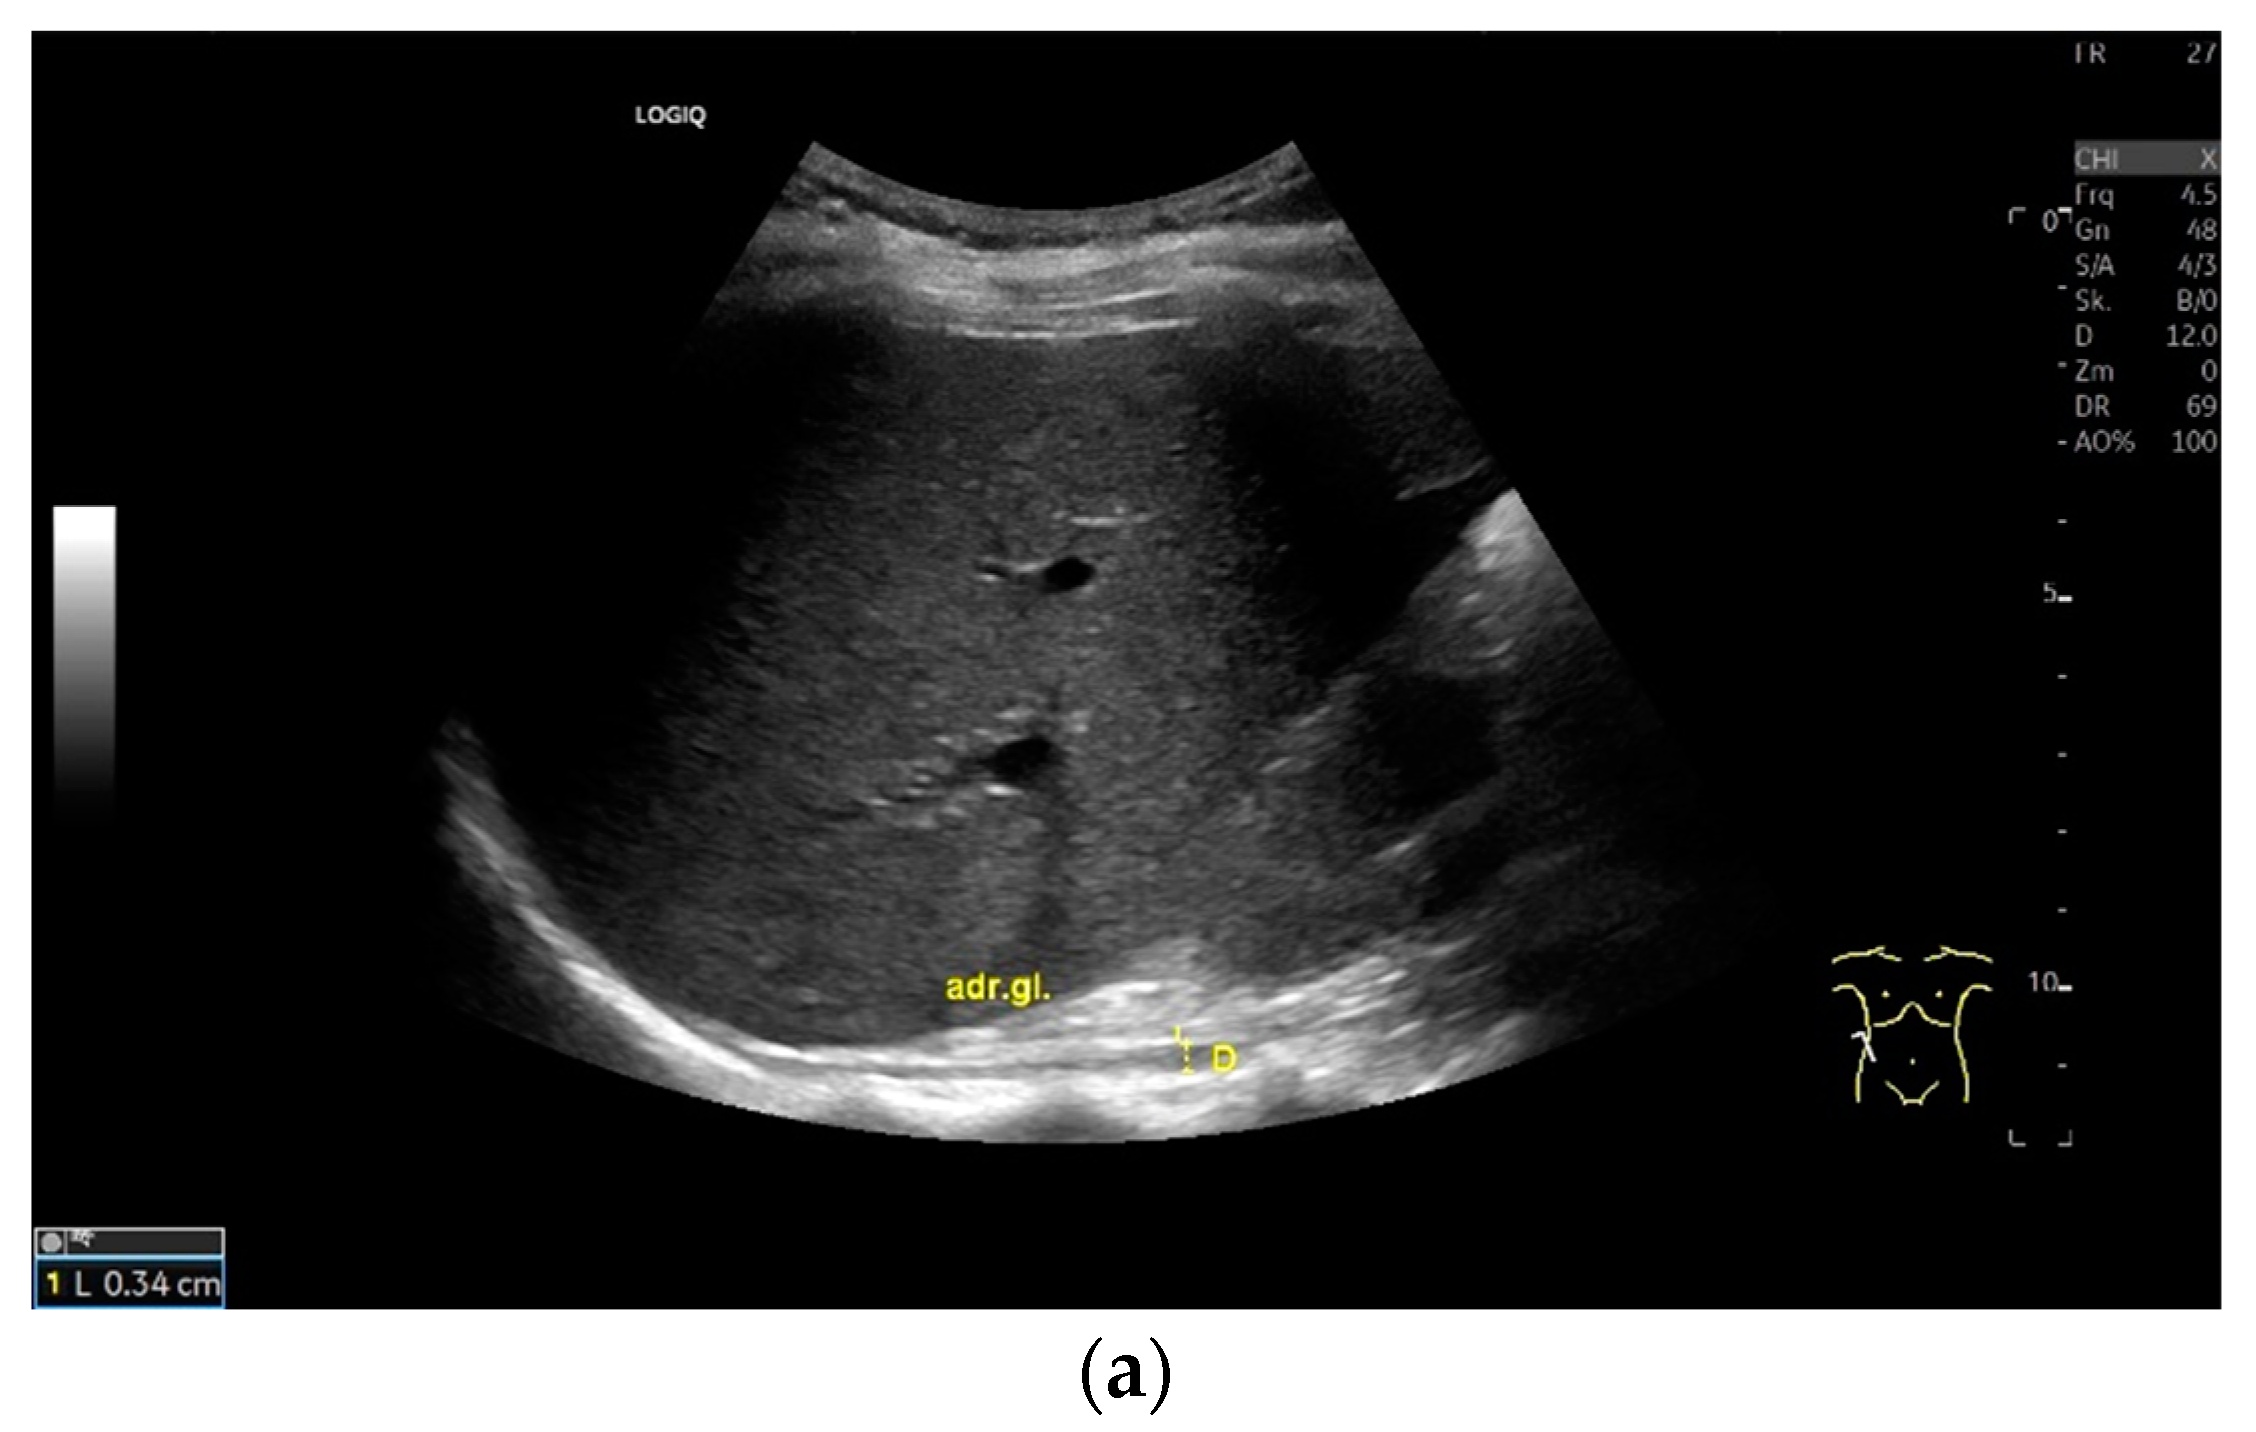

Subxiphoid: The diaphragm can be positioned directly subxiphoidally with a slightly sagittal transducer position on both sides next to the attachment to the sternum. The diaphragm limb can be demarcated to the right in the epigastrium in cross section between the aorta and the inferior vena cava. However, this is primarily of differential diagnostic importance, e.g., in relation to lymphomas, not for the actual assessment of the diaphragm (Figure 6).